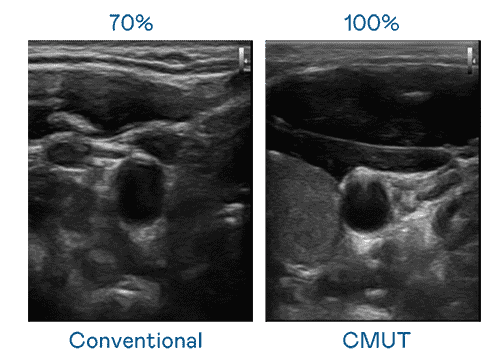

CMUT 技术是一种用电容式微机电元件来产生超音波讯号的技术。。与传统 PZT 压电式技术相比,,CMUT 频宽增加 30%,,,,更宽频的超音波讯号让影像解析度大幅提升,,,,是实现高影像品质医疗超音波扫描、、、、促进精准医疗发展的关键技术。。

大频宽带来超清晰影像

超音波影像的解析度高低,,首先取决于探头能发出的讯号频宽。。。。918.COM CMUT 可提供高清晰的超音波讯号,,,,提供高频宽、、、高灵敏度、、、、影像纹理细节更高的超音波影像,,协助医护人员缩短影像判读时间及利用精准的医疗影像进行诊断。。